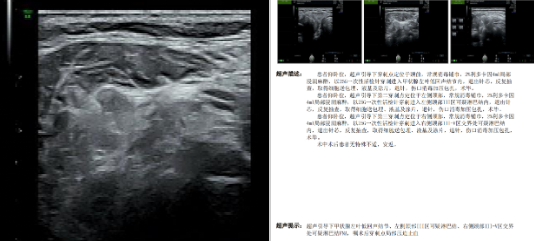

在此基础上,陆港院区超声医学科再度攻克技术难关,为一名外院提示甲状腺 4 类结节的患者开展超声引导下双侧颈部淋巴结及甲状腺可疑恶性结节细针穿刺术。该患者经魏炜副主任超声会诊,被明确为甲状腺左叶 5 类结节及双侧颈部广泛可疑淋巴结,符合穿刺指征。在详细告知患者病情、穿刺意义和风险并取得同意后,医疗团队在高分辨率超声实时动态引导下,精准避开甲状腺周围重要血管、神经及气管,分别对甲状腺左叶 5 类结节、左侧颈部 III 区可疑淋巴结、右侧颈部 III-V 区交界处可疑淋巴结进行穿刺,成功抽取满意的细胞学样本。操作过程顺利,患者无明显不适及并发症,术后恢复良好。

本次穿刺获取的高质量细胞学样本满足了病理诊断需求。甲状腺细胞涂片及蜡块切片中可见「细胞异型及核沟」,提示甲状腺乳头状癌,BRAF 基因 V600E 未检出到突变;左侧颈部 III 区及右侧颈部 III-V 区交界处淋巴结穿刺样本提示甲状腺乳头状癌转移,且淋巴结穿刺液测得甲状腺球蛋白(Tg)>500,呈高表达,为诊断提供了强有力的佐证,患者最终被确诊为甲状腺乳头状癌并双侧颈部淋巴结转移。